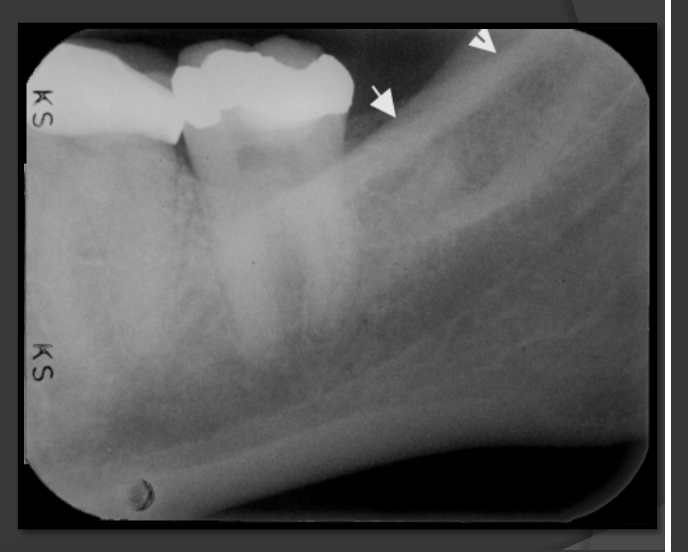

How does the coronoid process present in a radiograph?

-Radio-opaque

-Triangular/shark tooth shape pointing to the maxilla

-Point sits behind the maxillary molars